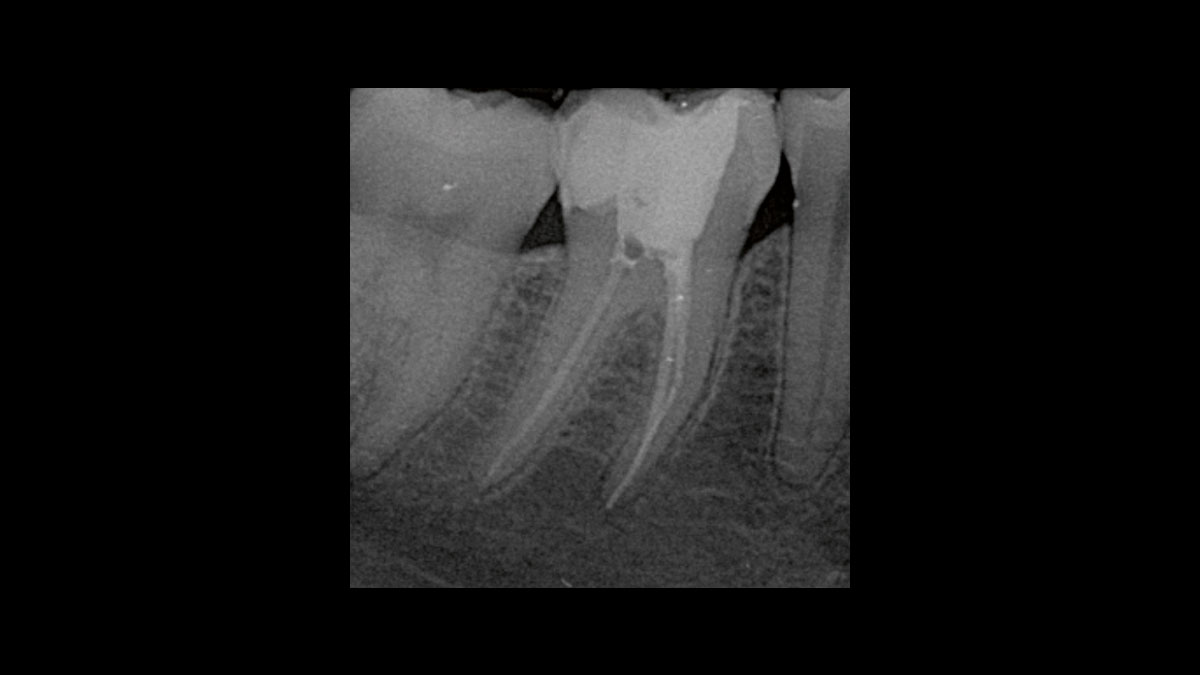

Endodontics

The following applications are presented in the videos and images:

• Endodontic germ reduction

• Gangrene germ reduction

Endodontic germ reduction